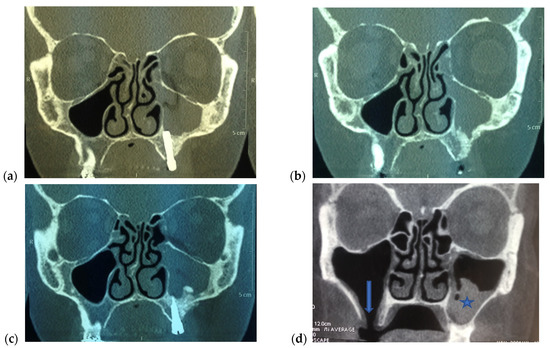

3. Presentation

4. Management